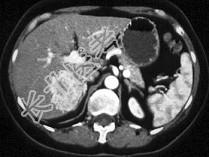

- 患者40岁,女性, 肝区偶然发现一个团块